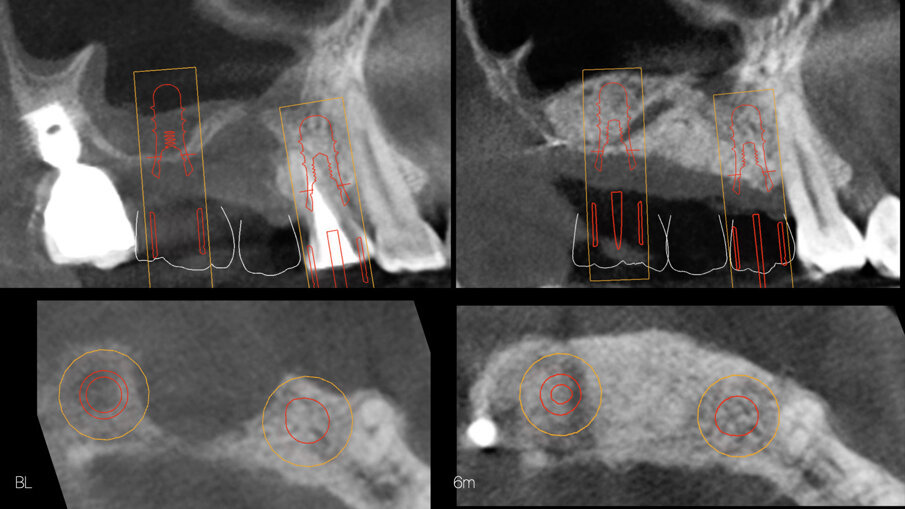

All’esame clinico e radiografico (Figg. 1, 2), si riscontra la persistenza della lesione endo-parodontale in sede 1.4, la presenza di un’atrofia ossea verticale nella cresta ossea edentula 1.5 associata a una deiscenza del pavimento sinusale sul fondo del difetto, e la presenza di una perimplantite severa a livello dell’impianto 1.7. Si riscontra inoltre una pneumatizzazione del seno mascellare destro in sede 1.6, con un’altezza ossea residua di ca. 1,5 mm.

A distanza di 6 mesi, previa acquisizione di una CBCT (Figg. 8-10), si procede con il rientro chirurgico nella sede ricostruita (Fig. 11). Scheletrizzato il mascellare ricostruito, si riscontra una parziale risoluzione del difetto verticale in sede 1.5 e il ripristino di volumi ossei idonei all’inserimento di impianti in posizione protesicamente guidata in sede 1.4 ed 1.6. Durante la preparazione dei letti implantari, si esegue il prelievo di due carote ossee mediante fresa trephine da 3.3 mm. Segue quindi l’inserimento di due impianti Tissue Level SP 4.1 x 8 mm (Straumann) e l’adozione di un protocollo di guarigione sommerso (Figg. 12, 13).

Fig. 8 - Guarigione a 6 mesi.

; Fig. 10 - CBCT al baseline e a 6 mesi - visione assiale e para-sagittale.